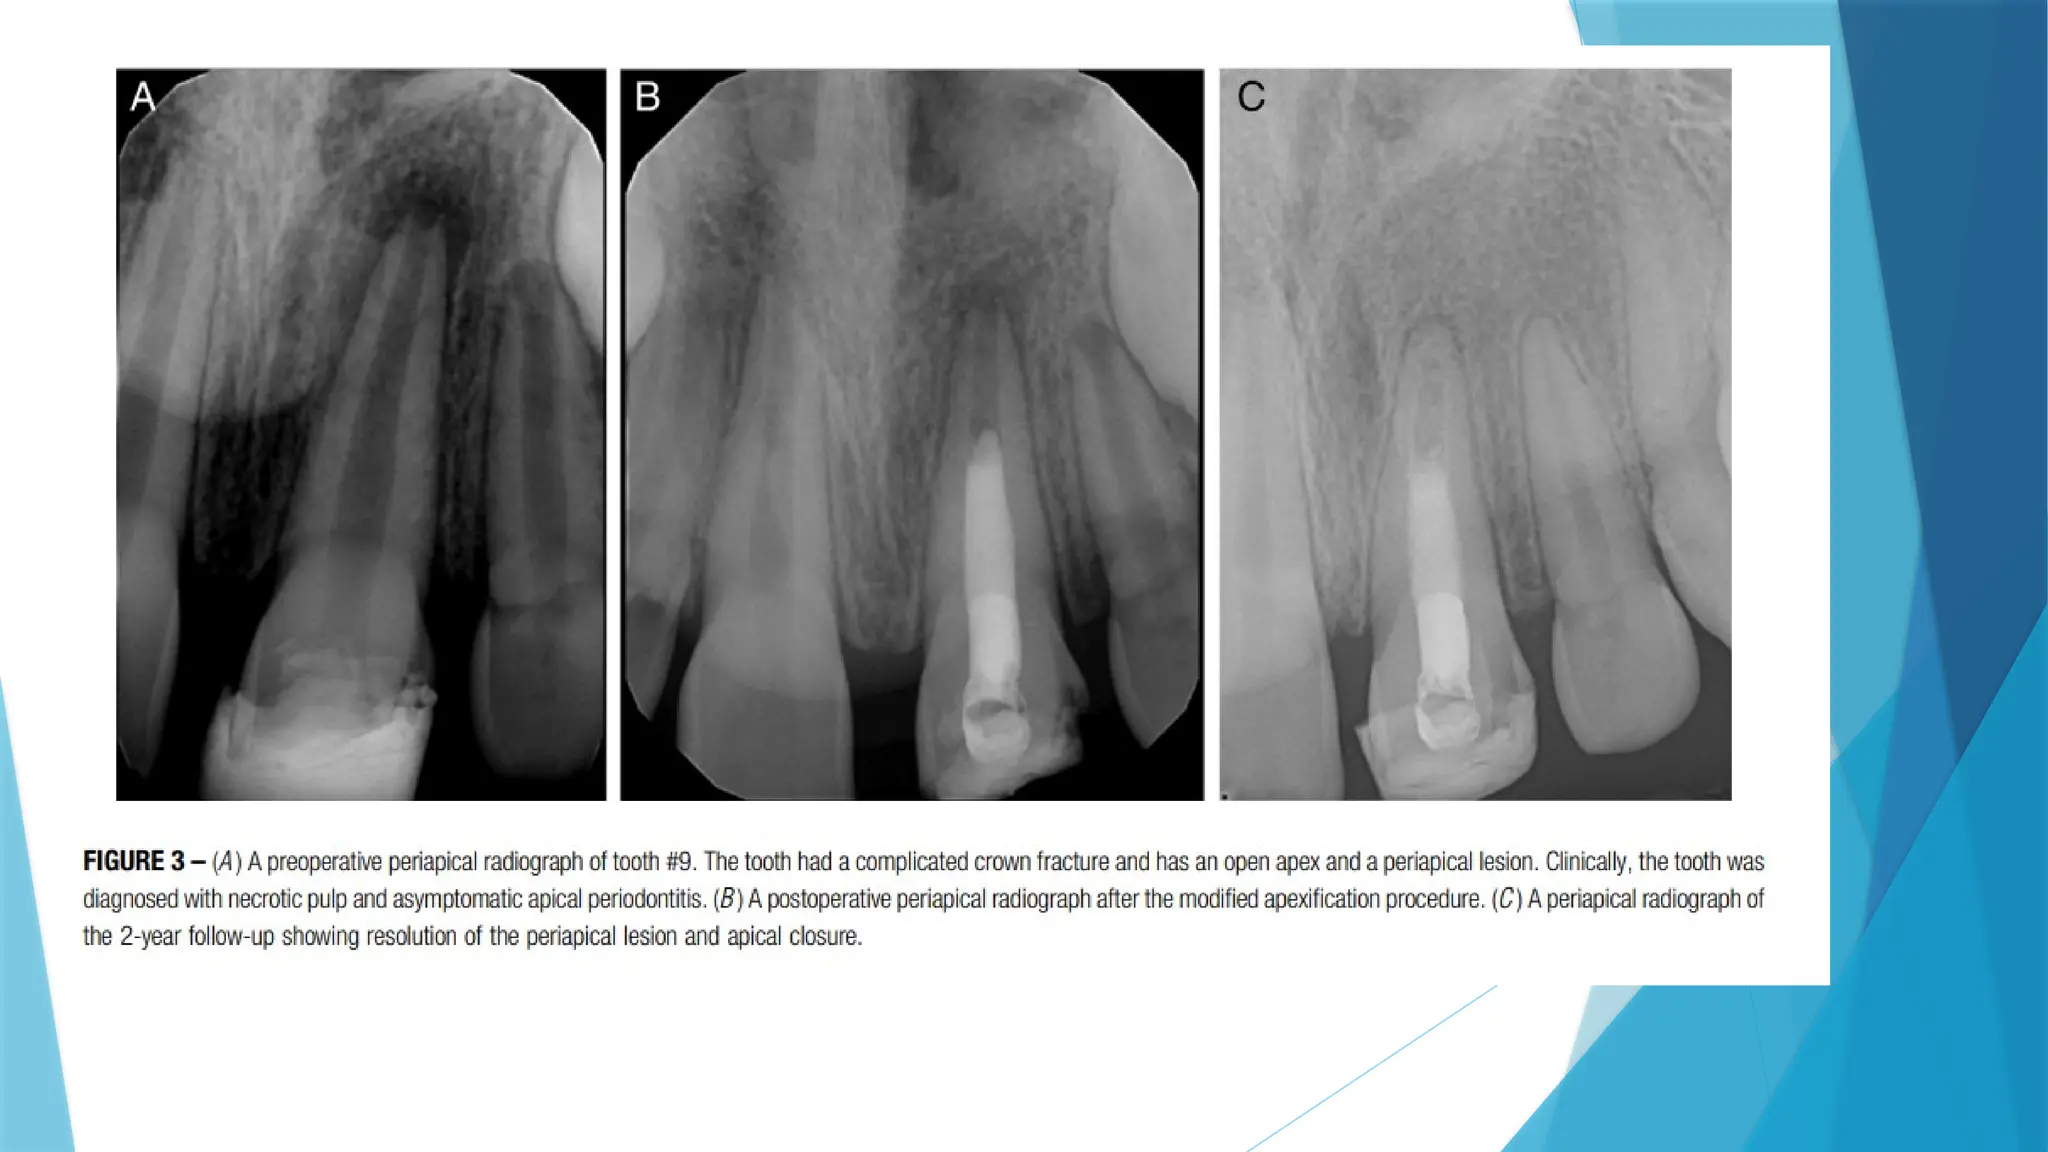

 Moreover, in 2020, Songtrakul et al. proposed a modified apexification

procedure, in which a 3- mm-thick MTA/Biodentine barrier is placed inside

the canal over a collagen matrix, which will be eventually resorbed and leave

an apical canal space unfilled for continued root development. The use of a

resorbable collagen matrix also helps to hold the material during its

application inside the root canal space, which allows for apical deposition of

mineralized tissue.